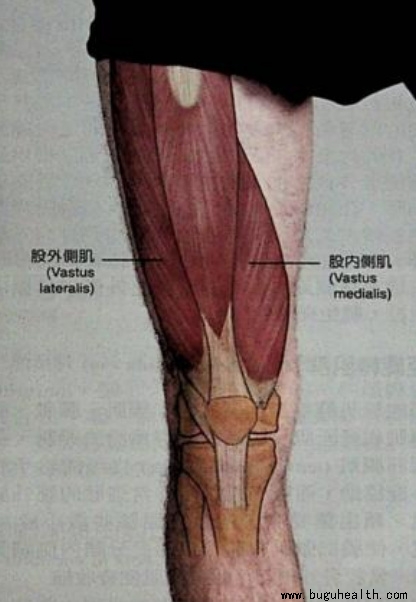

- 布骨医学科普:股内斜肌在康复训练中能被孤立练习吗? BuGuRMC布骨康复医疗中心 ,2023-11-29

- 在膝关节的运动中,良好的髌骨运动轨迹是非常重要的,本文主要讲股内斜肌的激活和练习两方面!.....